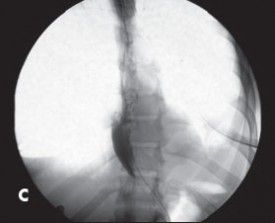

In an unrelated patient, barium swallow shows the classic “bird’s beak” appearance of the distal esophagus with proximal esophageal dilatation. The diagnosis was achalasia. Images courtesy Lakeisha Conley, MD, Christopher Knudsen, DO, Terry J. Hundley, MD, and Gregory W. Rutecki, MD.

Achalasia was suspected: high-resolution manometry confirmed type 2 achalasia. Subsequent timed barium esophagram showed moderate fusiform dilation of the esophageal column with tapering at the GEJ, a classic “bird beak” appearance (Figures). Given his desire for bariatric surgery for morbid obesity, POEM was selected as the procedure of choice because it would not violate surgical planes used for either a Roux-en-Y gastric bypass (RYGB) or sleeve gastrectomy.